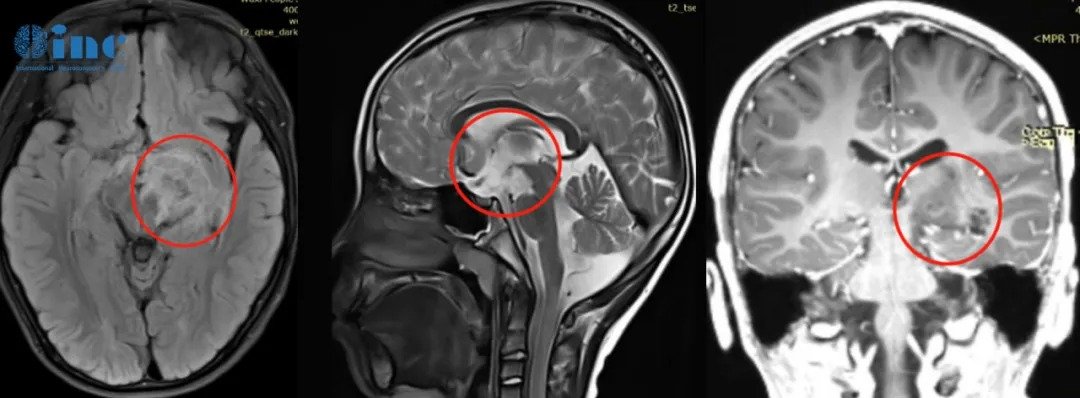

小磊术前MRI影像显示右额、颞、基底节区、侧脑室前角区巨大占位(胶质瘤),压迫丘脑,从右额白质延伸到岛叶和基底节前部,部分浸润丘脑和右下丘脑,并向颅内延伸到前连合和室间孔。

肿瘤血管丰富包裹大脑前动脉、大脑中动脉及其分支等。

▼术前术后影像资料:

术后情况:手术1年多后,复查核磁显示肿瘤的切除效果非常理想,局部血管及其他重要结构均得到完整保留。巴教授也为小欧如今的状态感到高兴。如今,小欧的癫痫发作频率明显减少,在随访时,他还可以用流利的英语与巴教授对话,像一个“小大人”般描述自己目前的身体状况,聪明又懂事,令一旁的父母深感欣慰。